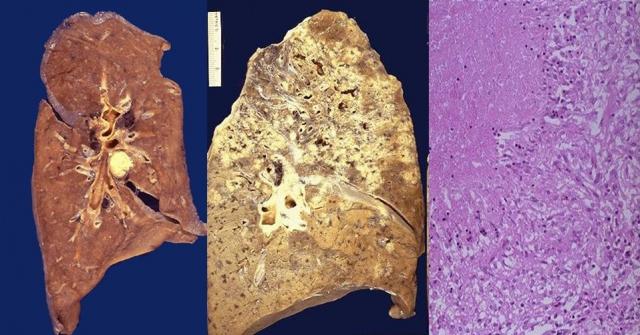

干酪样坏死(肺结核) |

资源描述:干酪样坏死属于凝固性坏死。坏死灶呈灰白色或黄白色,质地松软易碎,外观像干的奶酪或豆腐渣,故称为干酪样坏死。

文件来源:https://slideplayer.com/slide/4637873/

镜检,坏死组织结构消失,成为一片无结构的红色颗粒状。

干酪样坏死 |

资源描述:光学显微镜下的干酪样坏死

文件来源:https://classconnection.s3.amazonaws.com/576/flashcards/3624576/jpg/caseous_necrosis-14147C5461D67DEF354.jpg

肺结核 |

资源描述:左:隐性感染;中:空洞性结核(形成肺空洞);右:粟粒性结核

文件来源:https://medicalxpress.com/news/2015-05-simple-diagnostic-tuberculosis-humans.html